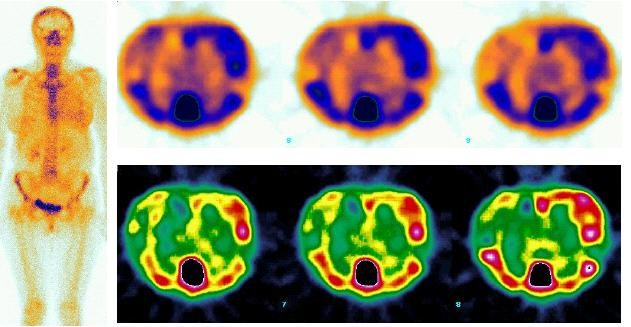

80-letá pacientka s oboustranným zánětlivým karcinomem prsu má za sebou radioterapii levého prsu, je po cyklické chemoterapii, probíhá hormonoterapie. Klinicky : St. sin.: Levý prs je tužší, patrny jizvy po zhojených defektech kůže a podkoží. St. dx.: V HVQ centrálně prominuje zarudlé ložisko průměru asi 15mm, zcela drobné lentikuly jsou hmatné difuzně podkožně. RTG: Bilaterálně difuzně zhrubělá struktura. Vlevo stacionární nález skupiny mikrokalcifikací centrálně a dorzálně. UZ vyšetření: St. sin.: Edém kůže, stacionární nález infiltrace v DVQ. St. dx.: V HVQ hypoechogenní solidní ložisko - v.s.kožní meta. Edém kůže pravého prsu. Histologické vyšetření z kožní excize lentikuly pravého prsu prokázalo v koriu a podkoží infiltraci dobře diferencovaným adenokarcinomem duktálního typu s ojedinělými ložisky nekrózy.

Výsledky : U první nemocné je patrno ložiskové zvýšení akumulace radiofarmaka v tumorózní tkáni pravého prsu s kalcifikacemi. Plošné zvýšení záchytu aktivity v okolí odpovídá kolaterálnímu edému. U druhé nemocné se zobrazuje výrazné zvýšení akumulace v jizevnatě změněné kůži i podkoží levého prsu a jeho stagnace v edému, dále vazba na skupinu mikrokalcifikací centrálně a dorzálně. Ložisko zvýšené akumulace v pravém prsu odpovídá kožní metastáze.

Scintigrafie skeletu je u diagnózy nádorové choroby prsu součástí stanovení stadia nemoci. Mechanismus vazby osteotropního radiofarmaka v kosti není přesně znám. Zčásti se váže na krystaly hydroxyapatitu, zčásti na mezibuněčnou hmotu bílkovinné povahy. Aktivita radiofarmaka se v karcinomu prsu vázala na kalcifikace v tumorózní tkáni, prokázala svou afinitu ke kalciu v jizvící se tkáni prsu i v nekroticky změněné kožní metastáze.

Pacientka s oboustranným zánětlivým karcinomem prsu